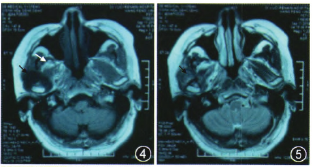

CT:右颞下颌关节有一不规则钙化高密度灶,呈哑铃形。外侧部分类似球形,突破关节腔位于颧弓下方、乙状切迹外侧及髁突前方;中间部分沿关节腔分布,呈盘状,与关节面间有潜在间隙,患例关节腔较健侧明显增宽;内侧部分跨越关节结节向前内斜形进入颞骨鳞部和蝶骨岩部,颅底骨质破坏(图1~3)。

图1CT可见病灶突出关节腔内外侧呈球状生长;图2颞下颌关节间隙不均一的高密度盘状钙化影,钙化影与髁突之间可见潜在间隙,病灶沿关节间隙分布,并向间隙内及外突出;图3病灶向前内突出至颞下窝.钙化物超越关节腔向外突出至面部,向内扩展至颅底;